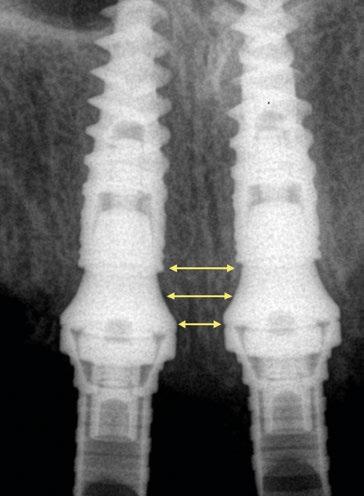

La importancia en la preservación del hueso crestal alrededor de los implantes y de las distintas estructuras del fenotipo periimplantario es vital para el mantenimiento y éxito funcional y estético a largo plazo (Ref.2). La utilización de conexiones cónicas robustas, mecánicamente estables y con cambio de plataforma como las de NobelActive® y NobelParallel™ pueden ayudar al mantenimiento del hueso crestal (Ref.3). Sin embargo, también es importante asociar este tipo de conexiones con la posición tridimensional del implante (Ref.4). Concretamente en el plano apico-coronal, la colocación de los implantes en posiciones subcrestales va a ayudar no solo a mantener el hueso, sino que va a permitir generar el espacio necesario para establecer una zona de transición biológica y protésicamente necesaria para desarrollar los perfiles de emergencia adecuados hasta llegar a la anatomía del margen gingival de la corona o perfil crítico (Ref. 5). Según las publicaciones, este espacio está establecido 3,5-4mm del margen gingival (Ref.6, Ref.7). Desde el punto de vista restaurador en implantes unitarios, es conocido que estos perfiles de emergencia deben ser diseñados con una transición suave. Partiendo desde un diámetro estrecho que progresivamente se va ensanchando. Siempre que el implante esté bien colocado tridimensionalmente el resultado será un perfil de emergencia cóncavo en el área subgingival. (Refs.8,9,10). La finalidad del concepto es proporcionar el máximo espacio horizontal para el crecimiento de tejido conectivo supracrestal alrededor de la interfase de titanio o pilar personalizado ofreciendo protección al implante a costa de maximizar el grosor y estabilidad a las estructuras del fenotipo periimplantario (Ref.11).

Con respecto al Multi-unit recto, su principal característica es la emergencia desde la plataforma del implante con un perfil completamente cóncavo. Por una parte, va a maximizar el efecto de “cambio de plataforma” en su parte más crestal a nivel de la plataforma del implante y por otra va a facilitar mucho más espacio para la creación de tejido conectivo supracrestal a lo largo de toda la transición hasta la plataforma restauradora. El perfil cóncavo del pilar también respetará en mayor medida los espacios comprendidos entre el pilar y el hueso interproximal (en el caso de una colocación subcrestal entre 1,5 y 2mm) para poder preservar al máximo las estructuras anatómicas presentes que soportarán las papilas periimplantarias.

Así como el diseño clásico de pilar hacía prácticamente imposible la colocación de implantes inmediatos en zona estética, el nuevo perfil cóncavo del pilar Multi-unit hace que se convierta en un pilar ideal para estas situaciones. La altura de pilar de 3 ,5 mm, hace que se pueda colocar la plataforma del implante en la posición corono-apical deseada con respecto al margen gingival sin involucrar el hueso adyacente y permitiendo desarrollar un mínimo perfil de emergencia restaurador más horizontal para soportar cenit y tejido interproximal. (Fig.6-7) Otra característica de diseño importante es la reducción del bisel de la plataforma res-

tauradora tanto en los pilares rectos como en los pilares angulados. Sin cambiar su diámetro clásico de 4,8mm ni su compatibilidad para atornillar y asentar cualquier aditamento restaurador de toda la gama Multi-unit, el nuevo pilar presenta una plataforma mucho más fina y estilizada que facilitará también su inserción incluso sin necesidad de utilizar la fresa “bone mill” o molinillo de hueso. De esta manera no solo se seguirá incrementando la preservación ósea, sino que también se reducirán los tiempos quirúrgicos al evitar tener que atornillar y desatornillar la guía del molinillo o “Bone Mill Guide”. (Figs. 8-12)

La colocación del implante inclinado de 30º siempre implica que la zona más mesial de la plataforma se encuentra en posición yuxtaósea y la zona distal en posición subcrestal. Clásicamente se debe utilizar el instrumento “bone mill” de 5,2mm (NP) o 6,2mm (RP) para poder insertar el pilar en la posición deseada. En la figura 14 (Fig.14) se observa una situación clínica comparativa donde se han colocado implantes inclinados con una orientación de 30º aproximadamente en dirección hacia los rebordes piriformes en una premaxila. Claramente se puede observar la cantidad de remodelación ósea provocada por el molinillo versus la preservación que ofrece la colocación el nuevo Multi-unit sin necesidad de acondicionar la cresta ósea. En configuraciones de tipo All-on-4®, en los implantes distales se produce una situación similar. El inconveniente que se puede producir en estos casos es la posibilidad de la aparición de una recesión de la mucosa periimplantaria alrededor del pilar precisamente por la combinación de quedar la zona sin soporte óseo y por el propio volumen excesivo que ocupa el pilar. Por el contrario, mediante la utilización de los nuevos perfiles no existe necesidad de remodelar el reborde alveolar y conjuntamente al menor volumen que ocupan los pilares, el tejido (si es suficiente) será capaz de mantenerse en mayor medida. En las figuras 15 a 18 (Fig.15-18) se describe una situación común donde se utiliza el pilar Multi-unit de 17º. En pacientes edéntulos o futuramente edéntulos en la zona de la premaxila. Para maximizar el hueso disponible en esta

za un pilar de 3,5mm de altura, existe el riesgo de reducir el espacio protésico y de nuevo que aparezca una recesión gingival si el implante se coloca a nivel crestal o ligeramente subcrestal (1-1,5mm). Independientemente de la altura seleccionada (2,5mm o 3,5mm), de nuevo, esta situación implica la remodelación ósea mediante bone mill para acomodar el pilar. En la Fig.10 se observa cómo queda la remodelación

circular en el implante en posición #1.2 versus la no remodelación de un pilar de nuevo perfil de altura 3,5mm en un implante colocado 2mm subcrestal. La limitación de los pilares de 17º clásicos es que emergen muy rápidamente hacia el diámetro de 4,8mm de la plataforma restauradora y de nuevo no existe espacio suficiente para el establecimiento biológico de la altura de tejido supracrestal. Claramente se observa en las

radiografías periapicales comparativas a los 3 meses de la colocación como el implante en posición #1.2 tiene signos de remodelación fisiológica. Hecho que no ocurre en los pilares con nuevos perfiles al ofrecer transiciones más suaves que respetan los principios biológicos.